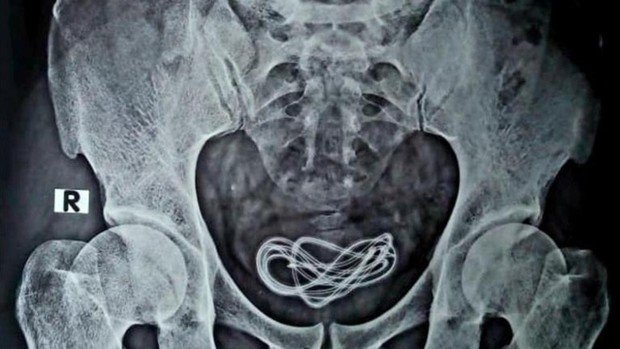

Estenosis Uretral Rx - Tratamiento de estenosis uretral con uretrotomia interna fria frente a laser.

Estenosis Uretral Rx : Mucosa uretral cicatriz circular y de longitud variable lesin.